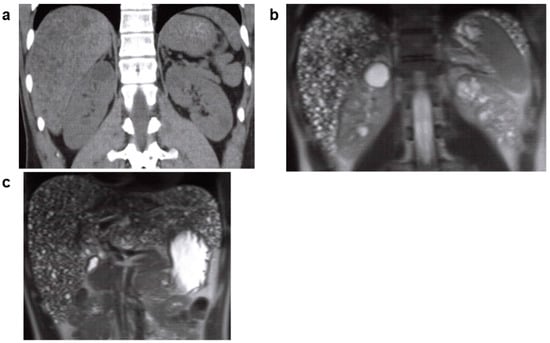

3.1. Autosomal Recessive Polycystic Kidney Disease (ARPKD)

| ARPKD | PKHD1, DZIP1L | AR | 1/8000–1/40,000 | Renal cystic lesions reflecting the expansion of the collecting duct with kidney function impairment, and congenital hepatic fibrosis characterized by bile duct dysplasia and intrahepatic periportal fibrogenesis. Thrombocytopenia, splenomegaly, and portal hypertension. |